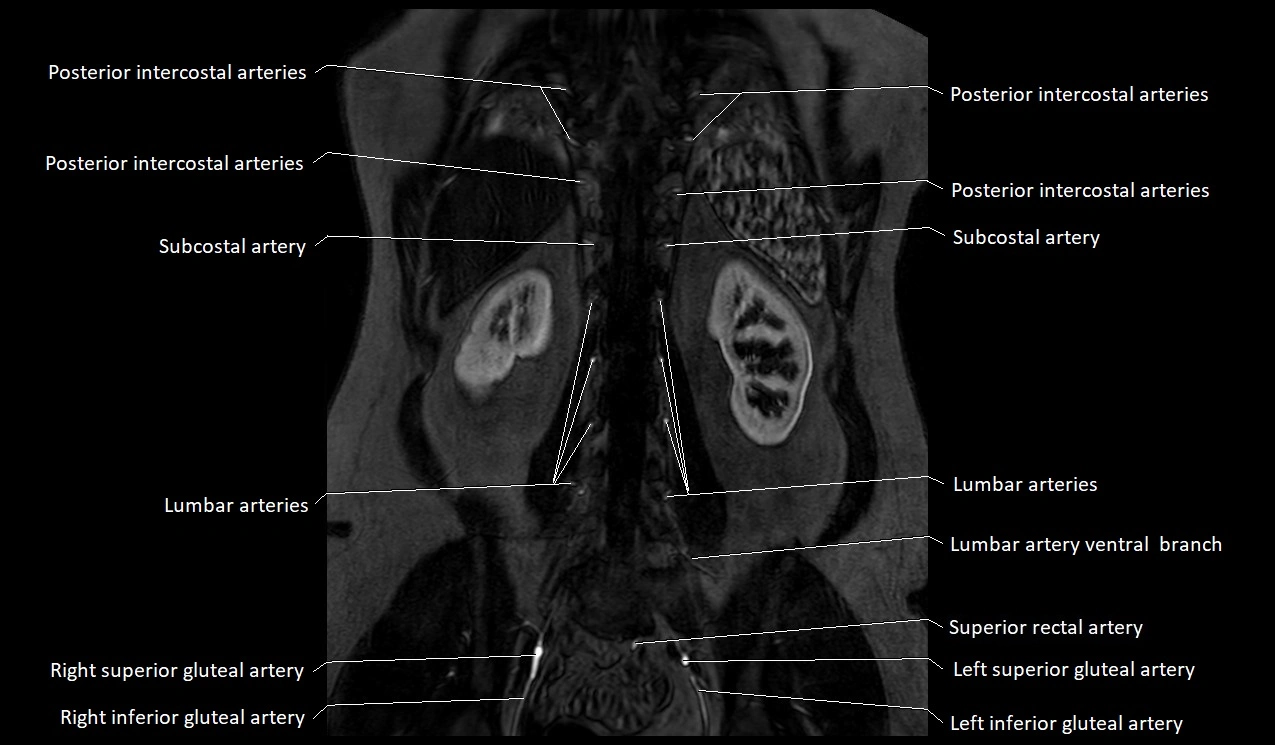

MRA Pelvis with Gadolinium:

-

Clearly delineates the origin, course, and anastomoses of the accessory obturator artery

Identifies connection with inferior epigastric artery, external iliac artery, or obturator artery

Excellent for detecting vascular variants prior to surgery

Useful in mapping pelvic vasculature in trauma, tumor embolization, or preoperative planning